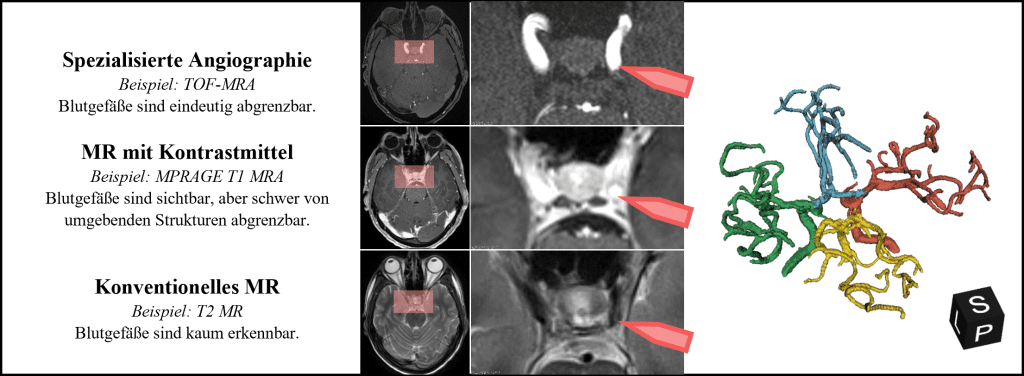

Wie einfach sich Blutgefäße in den Bilddaten von den umgebenden Strukturen abgrenzen lassen, hängt in erster Linie von der verwendeten Bildgebungsmethode ab. Die Magnetresonanzbildgebung (MR) bietet den Vorteil, dass sie nicht-invasiv ist und ohne den Einsatz von Röntgenstrahlen auskommt. Zudem stehen den Radiolog*innen unterschiedliche Sequenzen zur Verfügung, um verschiedene Gewebeeigenschaften zu betonen und so bestimmte anatomische Strukturen hervorzuheben. Die Time-of-Flight (TOF) Sequenz ermöglicht etwa den Blutfluss innerhalb der Arterien abzubilden, ist aber aufgrund des schwachen Kontrasts schlechter für die Beurteilung von Gehirngewebe geeignet als vergleichsweise die T2 Sequenz. Welche Sequenzen bei der Bildaufnahme zum Einsatz kommen, ist abhängig von der medizinischen Indikation und die Anzahl an verschiedenen Sequenzen wird zugunsten der Aufnahmedauer eingeschränkt. Bilddaten sind deshalb oft nicht verfügbar, was eine Beurteilung der Blutgefäße erschwert oder gar unmöglich macht. Abbildung 2 veranschaulicht die Sichtbarkeit von Blutgefäßen in unterschiedlichen MR-Sequenzen.

Abbildung 2: Die Sichtbarkeit von Blutgefäßen hängt stark von der verwendeten Bildgebungsmethode ab. In den Schnittbildern wird der gleiche Ausschnitt eines zerebralen Gefäßbaum (rechts) in drei unterschiedlichen Sequenzen abgebildet.